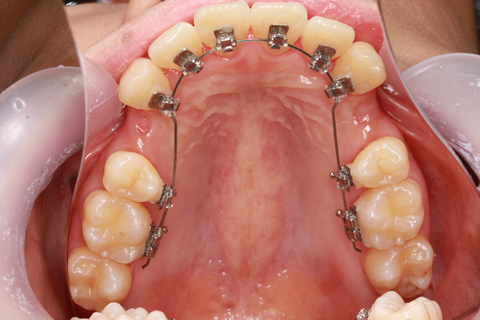

ハーフリンガル矯正1(上の歯のみ舌側矯正で治療)

治療前

治療中

治療後

- 年齢・性別

- 22歳女性

- 治療期間

- 1年8ヶ月

- 抜歯

- 上顎4番抜歯

- 治療費

- 110万円(税込み)

- 備考

- ハーフリンガル矯正

- 治療内容

- 上下前歯部凸凹の改善

- 施術の副作用(リスク)

- 裏側矯正では装置に慣れるまで発音しづらい場合がある。